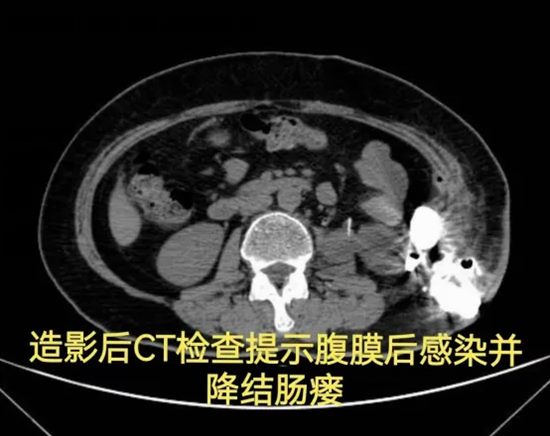

病情简述:56岁女性,两次腹膜后手术后出现降结肠瘘。

诊疗破局:按传统疗法,需先做结肠造口(挂粪袋),等半年后再做二次手术还纳。为减轻患者痛苦,团队制定“清创、控感、一期修复”三步法,实施腹腔镜下瘘切除+一期结肠端端吻合术。术后一周患者正常进食,免去了半年造口之苦。

技术体现:精准的术前评估与微创技术,让创伤最小化与疗效最大化不再是单选题。